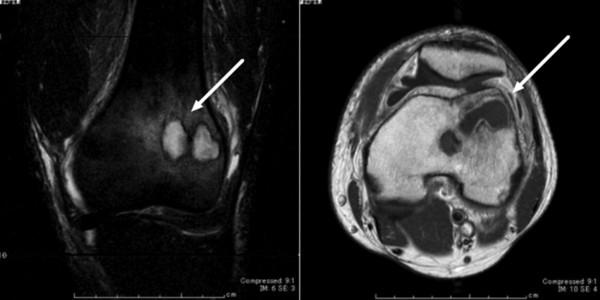

A 44-year-old Japanese immunocompetent man presented with acute-onset left knee pain and swelling. He had no history of food poisoning, and his most recent travel to an endemic area was 19 years ago. Salmonella enterica serovar Ohio was identified from samples of bone abscess and joint tissue. Arthrotomy and necrotic tissue debridement followed by intravenous ceftriaxone was successful.

一名44岁免疫功能正常的日本男性因急性发作的左膝疼痛和肿胀前来就诊。他无食物中毒史,最近一次前往流行地区是在19年前。从骨脓肿和关节组织样本中鉴定出肠炎沙门氏菌俄亥俄血清型。关节切开术和坏死组织清创术,随后静脉注射头孢曲松治疗取得成功。